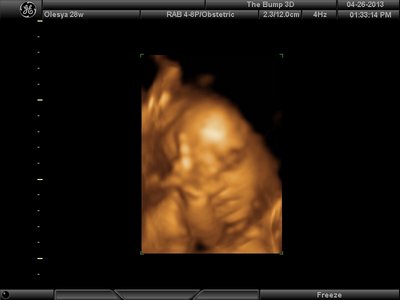

Вот, наш губошлёп:)

| Вложения: |

FACE.png [ 91.95 КБ | Просмотров: 1241 ]

Ой, Ксюнь, класс!!! Я говорю у вас у всех очертания носика, губок видны отлично...у моей же все размыто как-то и везде разное. На одной фотке вообще не нос а аэродром. Я ничего не поняла. Но УЗИстка сказала что она очень близко к плаценте мордашкой была поэтому так мутно все. Я надеюсь они мне переделают бесплатно все же. Я бы очень хотела. Так рассмотреть охото как следует, за это ведь и платила как никак..:-)